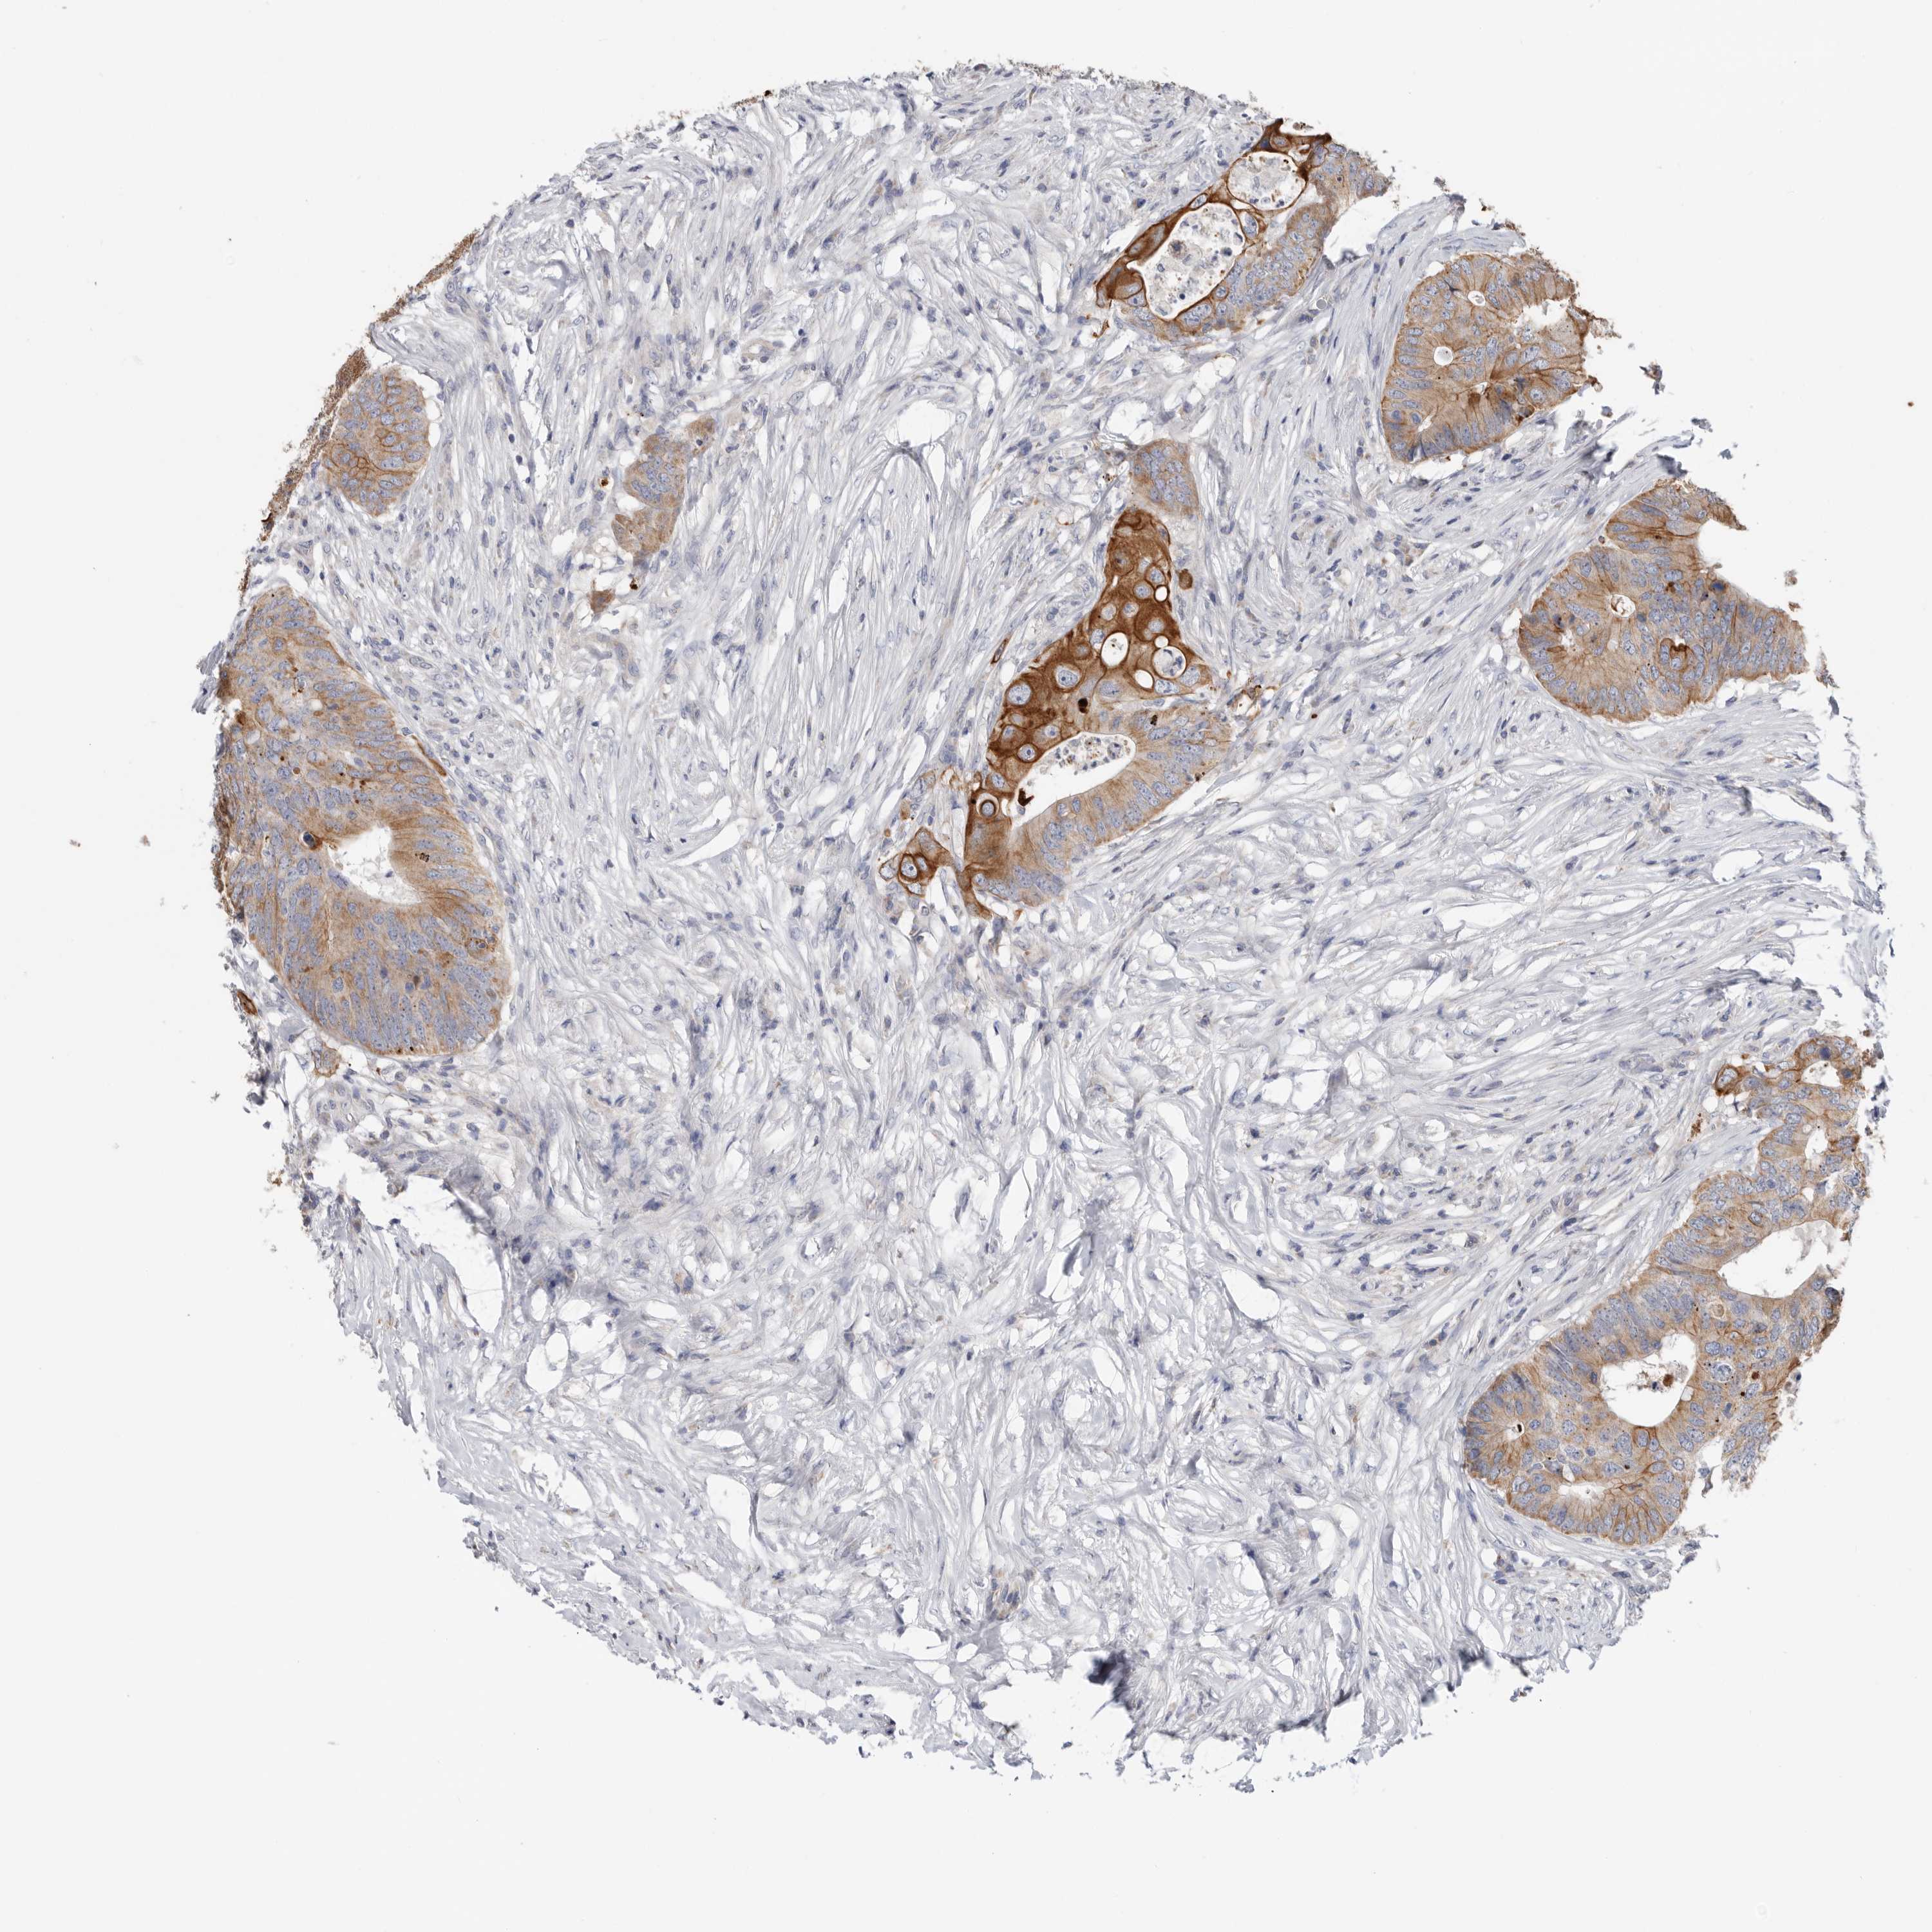

CANCER COLORECTAL CANCER Show tissue menu

Colorectal cancer

Human cancer

Colon adenocarcinoma